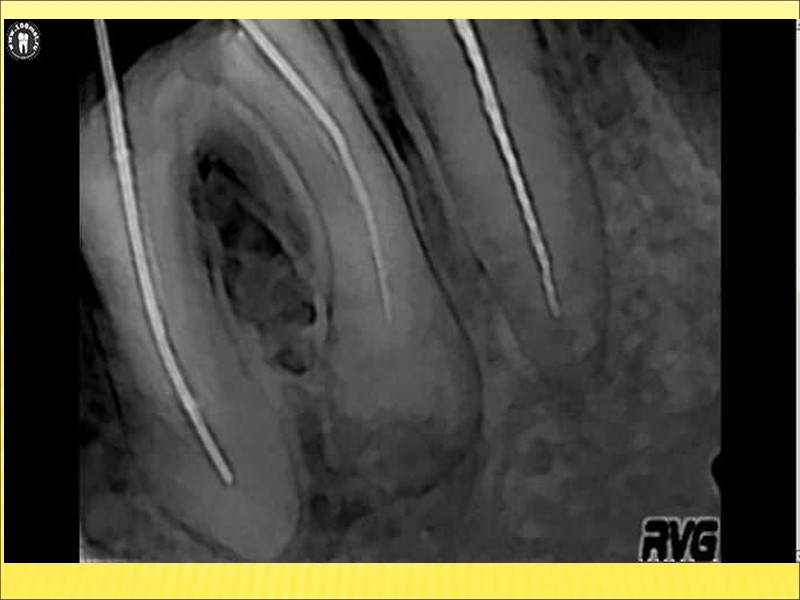

Объективно: в ранних стадиях отмечается веретенообразное вздутие тела челюсти; при этом опухоль представляется гладкой или слегка неровной – бугристой, плотной (костной) консистенции. Кожные покровы над опухолью в цвете не изменены, собираются в складку; иногда несколько бледноваты. Позднее появляются признаки кистозного новообразования: очаги пергаментного хруста, флюктуация; кожа над опухолью истончается, бледнеет, появляется видимая сосудистая сеть, она трудно собирается в складку. Со временем кожа истончается и даже может доходить до изъязвления над местами наиболее выраженных костных выпячиваний. Регионарные лимфоузлы не увеличены при том условии, если содержимое кистозных полостей еще не нагноилось и к опухолевому процессу не присоединилось воспаление кости. Зубы в области опухоли обычно достаточно устойчивы, но могут быть и несколько расшатаны (при наличии хронического воспалительного фона). Слизистая оболочка десны нормальной окраски или цианотична. Рентгенографические данные разнообразны. Важнейшей рентгенологической чертой адамантином является различная степень прозрачности полостей. Для гистологического строения адамантином характерно отсутствие четких границ опухоли, наличие отростков и выступов, инфильтрирующих окружающие ткани. Этим определяется необходимость радикального удаления опухоли, отступая от рентгенографически определяемых ее очертаний.

На рентгенограмме челюсти определяется лишенный структуры участок кости, имеющий более или менее четко очерченные границы. Корни соседних зубов оказываются отодвинутыми. Костная граница периодонтальной щели зуба, от которого растет киста, разрушена и потому на рентгенограмме не контурируется. При пункции кистозной полости (толстой иглой) получают янтарно-светлую жидкость с примесью холестериновых зерен – блесток. симптомы: внешне заметная деформация кости; симптом пергаментного хруста, продавливаемой пластмассовой или резиновой игрушки; еще симптом флюктуации; наличие специфического пунктата (янтарный цвет, блестки холестерина); дивергенция корней зубов. В случае нагноения ко всем этим объективным симптомам присоединяются покраснение, отечность и инфильтрация окружающих тканей, а также жалобы больных на более или менее выраженную боль в области кисты и повышение температуры тела. Если нагноение содержимого кисты переходит в острый остеомиелит челюсти, появляются симптомы этого заболевания.